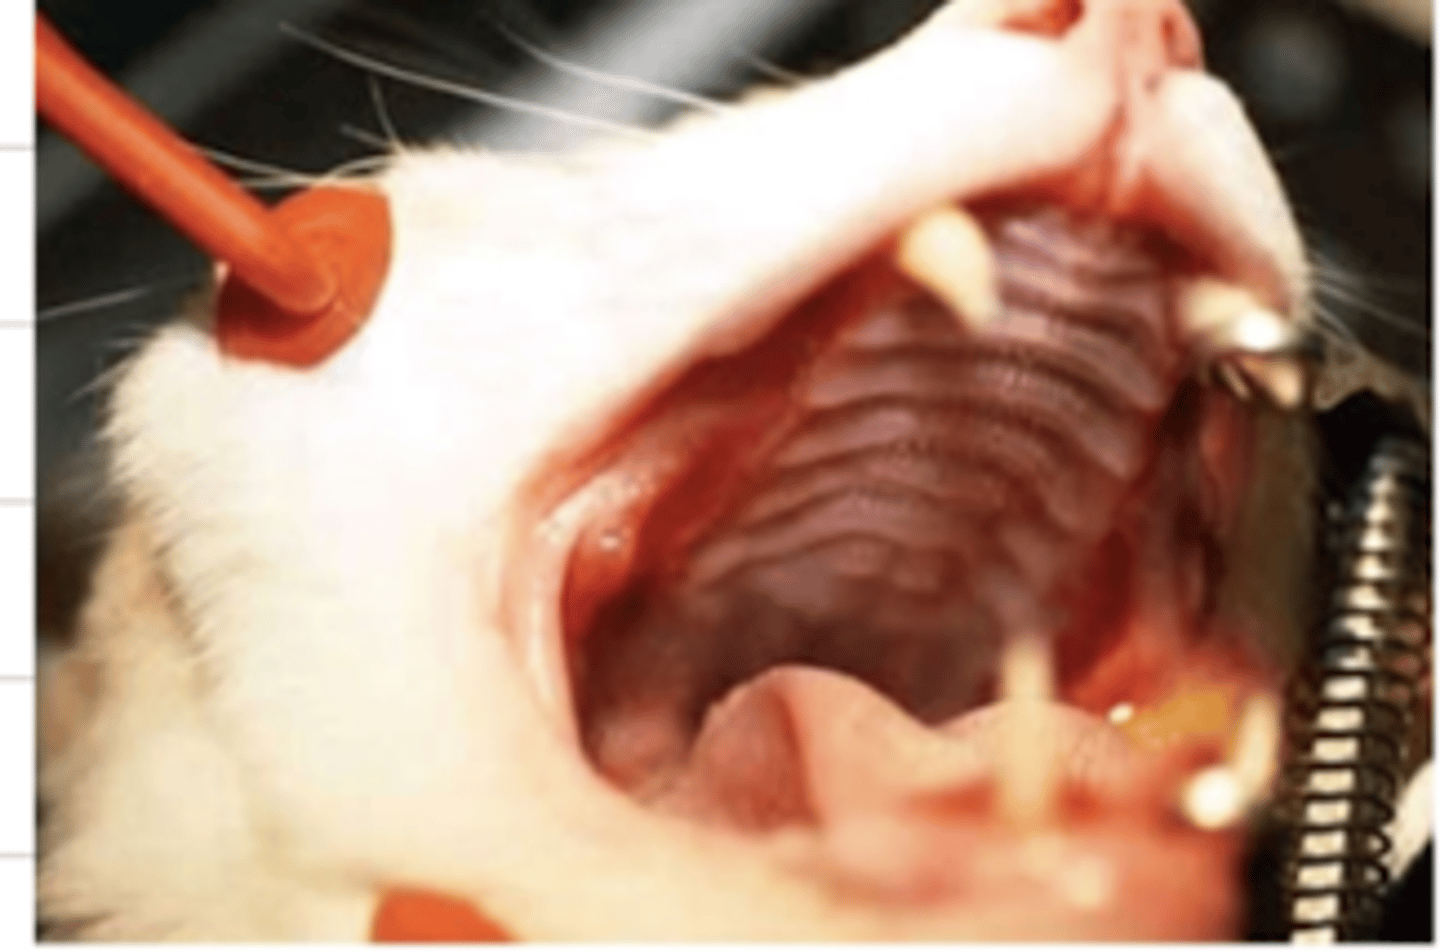

glossitis

what is the medical term for this issue?

what might be possible etiologies of glossitis?

pine processionary caterpillars- dogs commonly lick them, and they damage their oral cavity, commonly causing glossitis